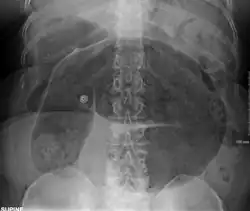

Plain X ray of a cecal volvulus -